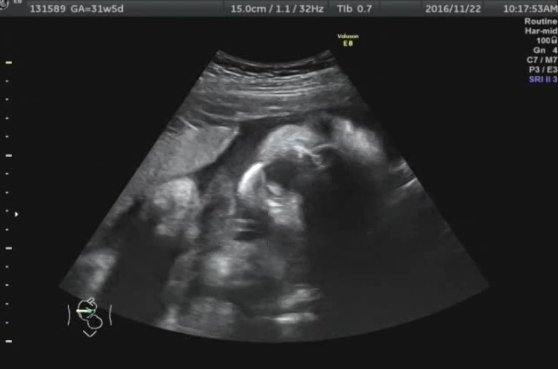

31週0日(31w0d・男の子)|あみ0524 さん(27歳)

エコー写真撮影時のエピソード:

はっきりと初めて横顔が見えてうれしかったです! 目がクリクリで(エコーだとみんなそうなのでしょうが…)めちゃめちゃかわいい子だねー!と親バカ、じじばばバカでエコー写真を見ました。

このエコー写真を撮影したとき、しゃっくりをしていたり、指吸をしていたり、お腹の中でこんな風に過ごしているんだなと感動しました。